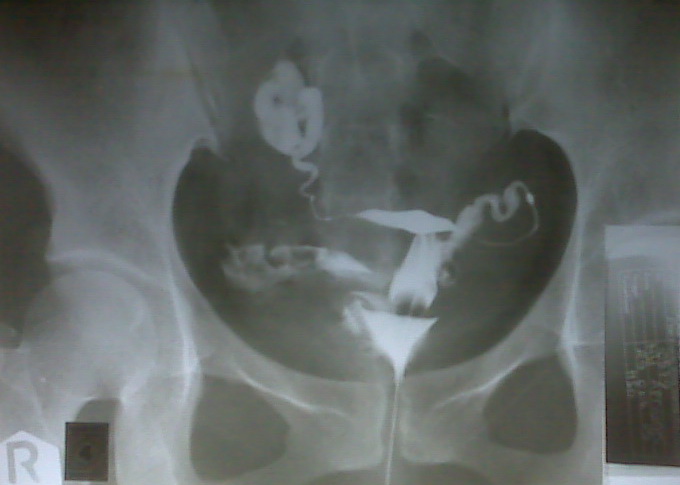

Cara deteksi tuba fallopi dengan hsg (hysterosalpingogram) 8.1.

Tabung falopi, atau tuba fallopi, adalah saluran yang menghubungkan ovarium dengan uterus. Tempat terjadinya konsepsi tempat pertumbuahn dan perkembangan hasil konsepsi sampai mencapai bentuk blastula yang tuba fallopi. Ampula, yaitu bagian terluas dari tuba falopi, biasanya merupakan tempat terjadinya fertilisasi atau pembuahan yaitu pertemuan sel sperma. Infundibulum, merupakan bagian tuba falopi yang memiliki fungsi sebagai tempat melekatnya fimbriae.